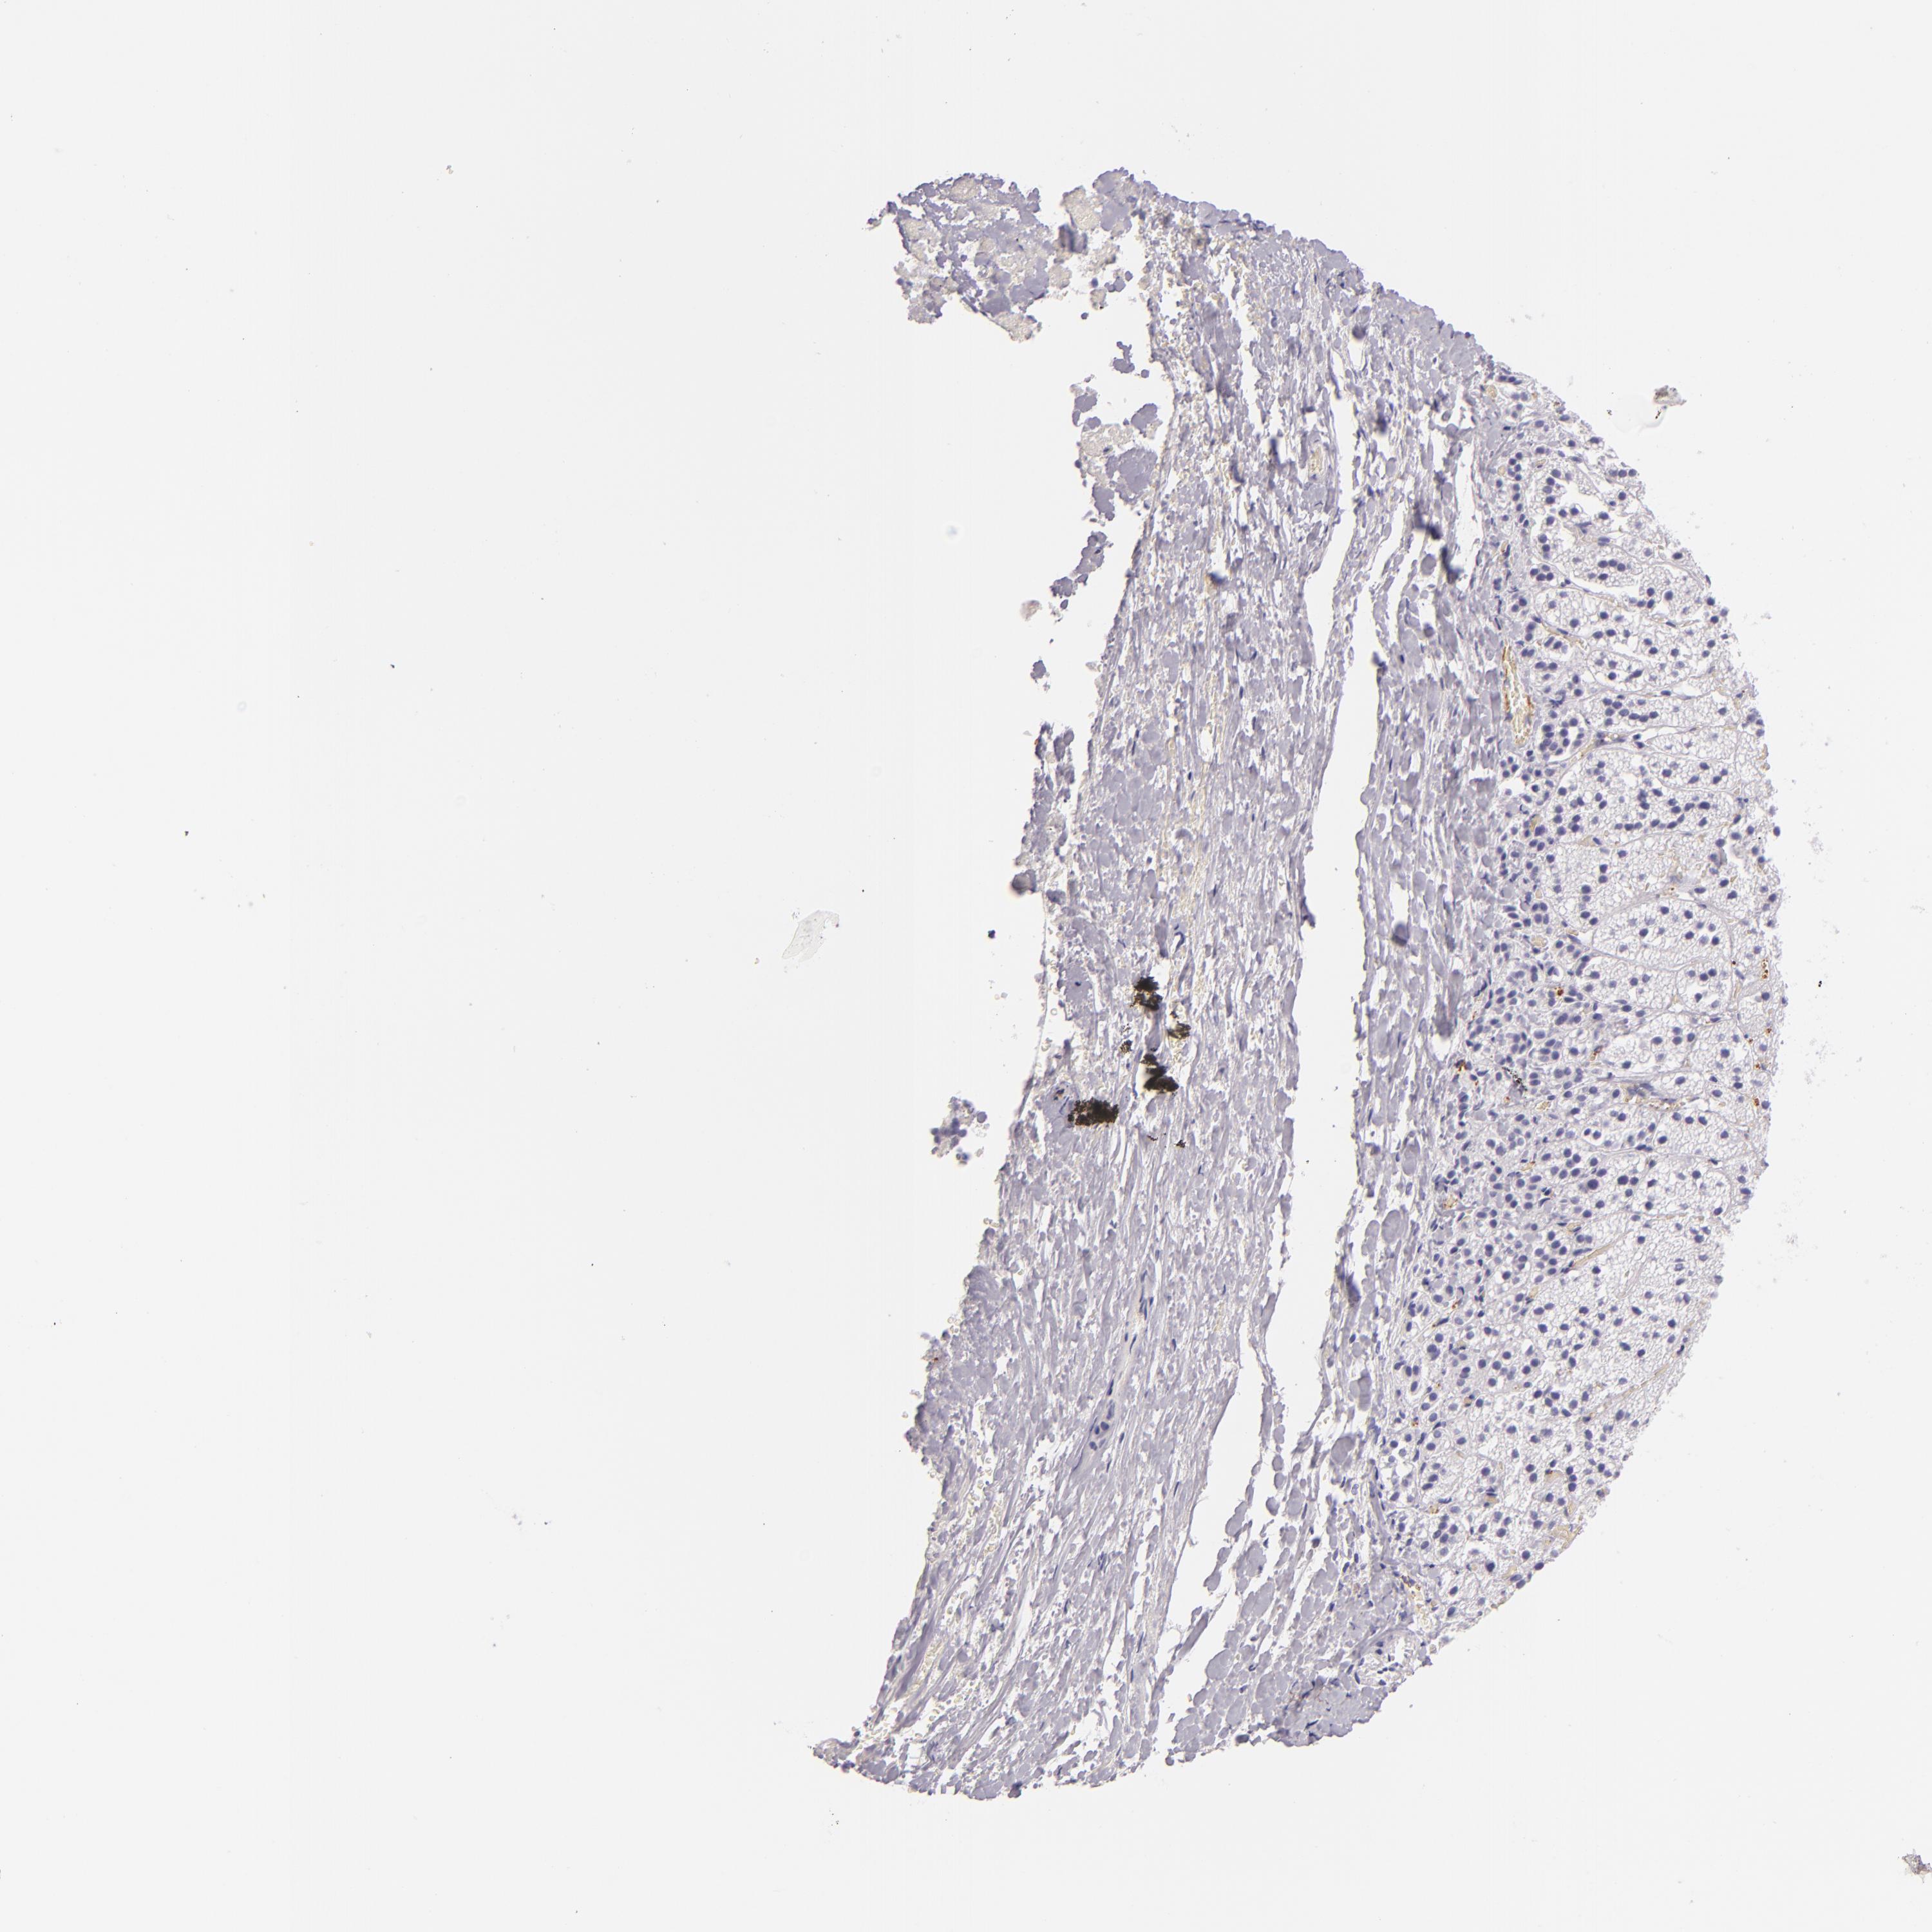

ADRENAL GLAND - Antibody stainingi

Antibody staining in the annotated cell types in the current human tissue is reported as not detected, low, medium, or high, based on conventional immunohistochemistry profiling in selected tissues. This score is based on the combination of the staining intensity and fraction of stained cells.

Each image is clickable and will lead to virtual microscopy that enables deeper exploration of all samples and also displays staining intensity scores, fraction scores and subcellular localization as well as patient and tissue information for each sample.

Antibody HPA002655Antibody HPA005990Antibody CAB002145

Glandular cells LowNot detectedNot detected